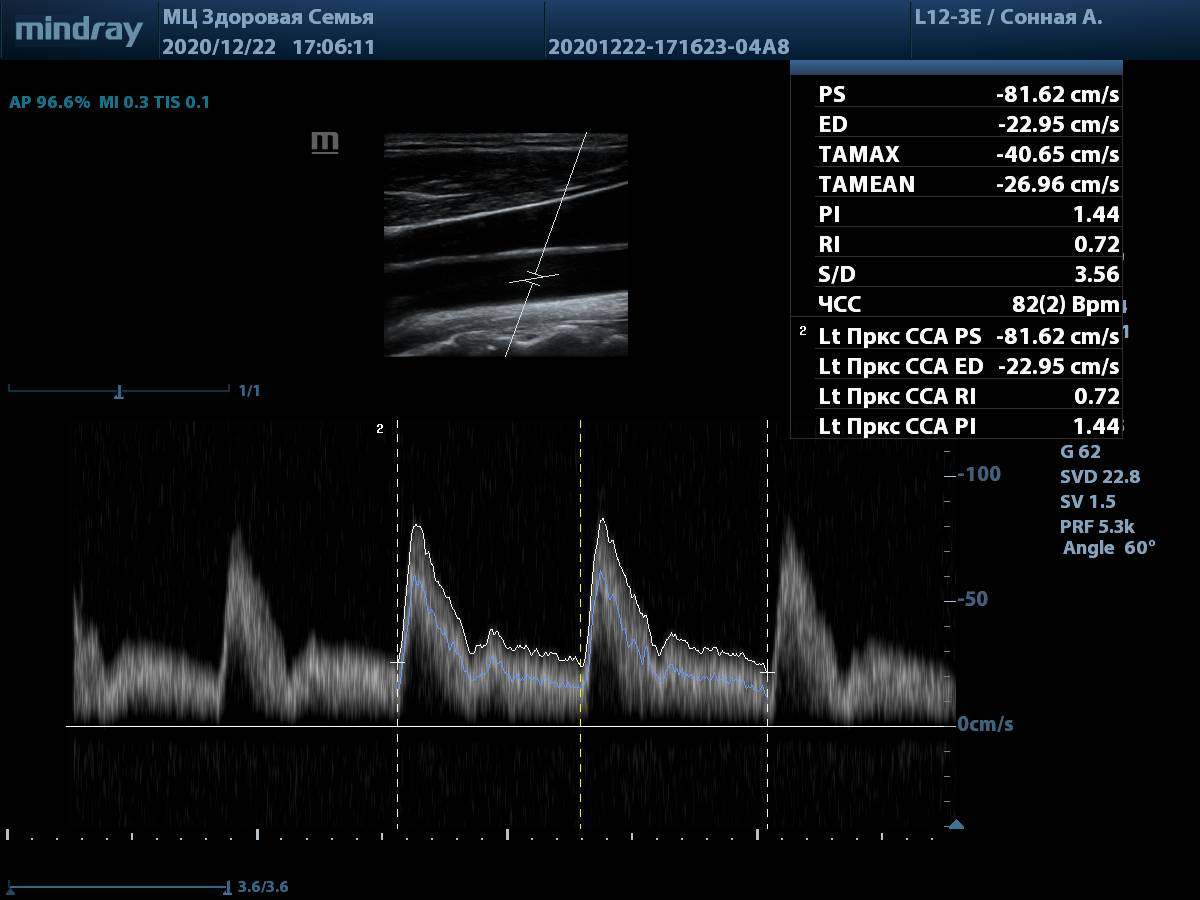

9. Общая сонная артерия, PW-допплер. Автоматическая трассировка игнорирует мелкие артефакты, четко повторяя спектр, а также использует несколько комплексов для снижения погрешности. Для отправки результата в отчет достаточно выбрать параметр в меню измерений.

Общая сонная артерия, автотрассировка